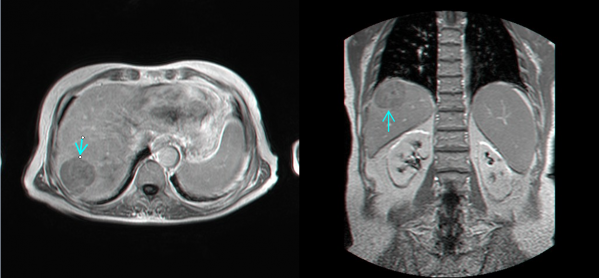

- בדרך כלל אין צורך בביופסיה מחטית של הנגע בתנאי שניתן לראות ב- CT מאפיינים קלאסיים ל- HCC. כיוון שה- HCC היא שאת מאוד וסקולרית הרי שהיא "נצבעת" מהר וחזק בשלב ההזרקה ויש שטיפה מהירה בשלב הפורטלי המאוחר (תצלום 30.10-33.10).

| תצלום 30.10: שאת בכבד הנראית ב- CT. מימין HCC הבולטת על פני הכבד. משמאל פגם מילוי בכבד כביטוי לשאת בכבד (החץ מצביע על השאת). | |

|---|---|

- MRI הוא אמצעי טוב להדגמת השאתות, מקומן האנטומי ויחסן לכלי הדם בכבד (תצלום 34.10). נמצא שה- MRI הוא יותר רגיש ויותר ספציפי ביחס ל- CT, אולם יותר יקר ממנו.